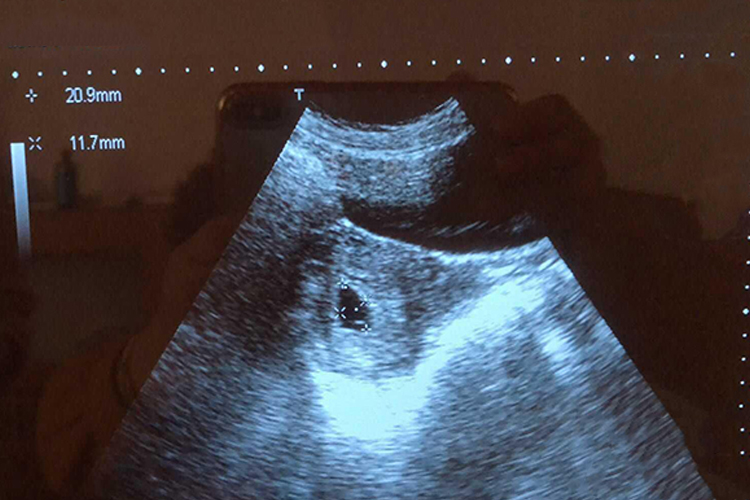

经腹超声一般在孕第5-5.5周才能见到明显的孕囊,而经阴道超声会在4-4.5周可发现孕囊。怀孕32天即怀孕4周末,多数会经阴道超声发现圆形或椭圆形的孕囊,孕囊囊壁完整无缺损,厚度基本均匀,回声强度接近一致。孕囊位于子宫体部,呈偏心性。